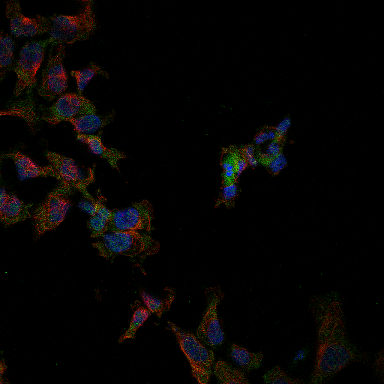

Medical_MultiLabel_Image_Classification

2563.png